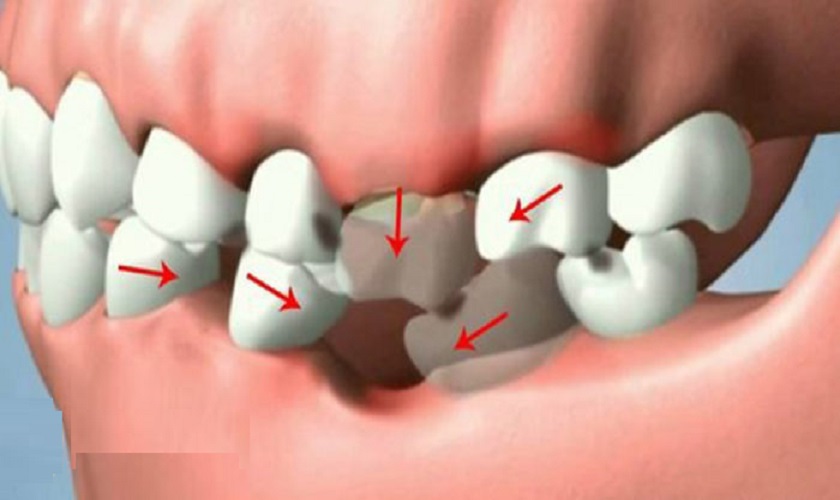

Vì là chiếc răng có ý nghĩa quan trọng nên việc nhổ răng số 7 cần phải được cân nhắc kỹ càng. Mất răng số 7 không được phục hình có thể dẫn đến những hậu quả nặng nề như xô lệch hàm, tụt nướu, tiêu xương, biến dạng mặt,…

Mất răng số 7 gây xô lệch cả hàm răng